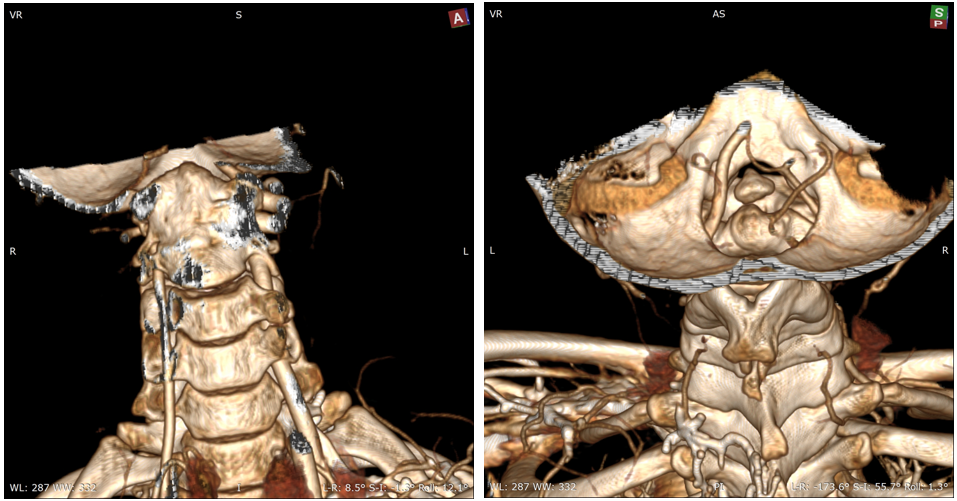

女,13岁,154cm,57kg

• 6个月前病人出现颈部活动受限,3个月前出现左手力弱

影像资料:

诊断:

• 齿状突小体

• 寰枢椎脱位

治疗:

• 后路关节松解寰枢椎复位内固定融合术

• 前路关节松解,后路寰枢椎复位内固定融合术

• 前路TARP技术

• 前路齿状突切除,后路内固定术